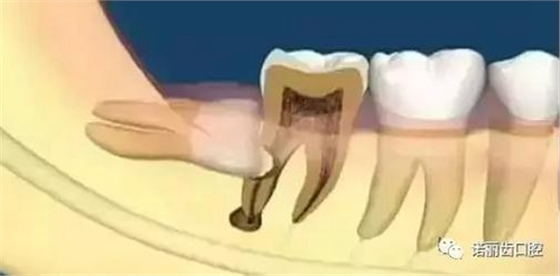

智齒蛀牙

如果智齒出現(xiàn)比較深的蛀牙,特別是需要根管治療的,一律建議拔除。